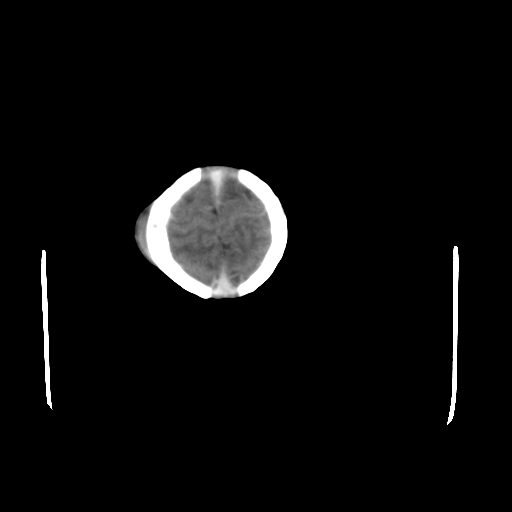

男,12天,自然分娩,其母发现右顶部头皮包块逐渐增大。

右顶部头皮血肿

右顶部头颅血肿(骨膜下血肿)

右顶骨呈膨胀性改变,骨纤维结构不良?

右顶部头皮血肿。

右顶部头皮血肿,可能是产道挤压所致。以后会慢慢恢复。

鉴别:骨膜下血肿,一般为产伤,应用产钳之类的吧

疑问:患儿脑白质密度比较低,基底节区密度比较高,类似于“双圈征”脑沟密度也偏高。该婴儿可有别的异常吗?反射正常吗?评分能达到5分吗?如果正常,就随诊观察吧。不正常要考虑到缺血缺氧性脑病。